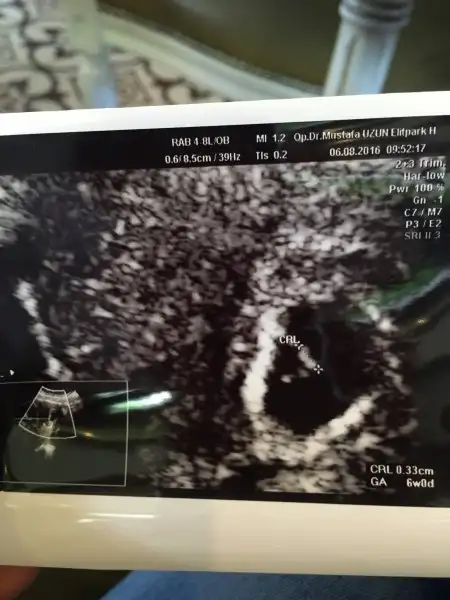

Crl yazan kısım bebek mm den bahsediyoruz zaten kese o kadar küçük olmaz

Evet bebek o. Erken davranmış seninki.Crl yazan kısım bebek mm den bahsediyoruz zaten kese o kadar küçük olmaz

Kağıtta da tam 6 haftalık yazıyor zaten

Erken döllenme bence çünkü erken görmüşsün bebeğiO hafta doktorun o bebeği sınıra aldığı noktaya göre değişiyomuş. Bebek biraz daha büyüyünce çıkar net haftası dedi.